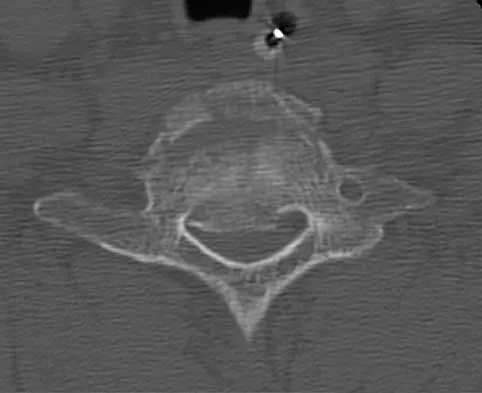

Figure 25 shows the CT scan of an adult patient who has neck pain following a motor vehicle accident. What is the most likely diagnosis?